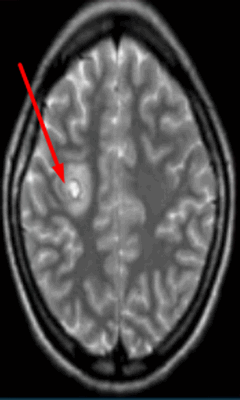

Абсцесс головного мозга на МРТ (указан стрелкой)

Гиперинтенсивные очаги

Выявление гиперинтенсивных, т.е. ярко выделяющихся на МР-сканах, очагов заставляет специалиста подозревать опухоль головного мозга, в том числе метастатического происхождения, гематому (в определенный момент от начала кровоизлияния), ишемию, отек, патологии сосудов (каверномы, артерио-венозные мальформации и пр.), абсцессы, обменные нарушения и т.п.

Опухоль головного мозга на МРТ (указана стрелкой)